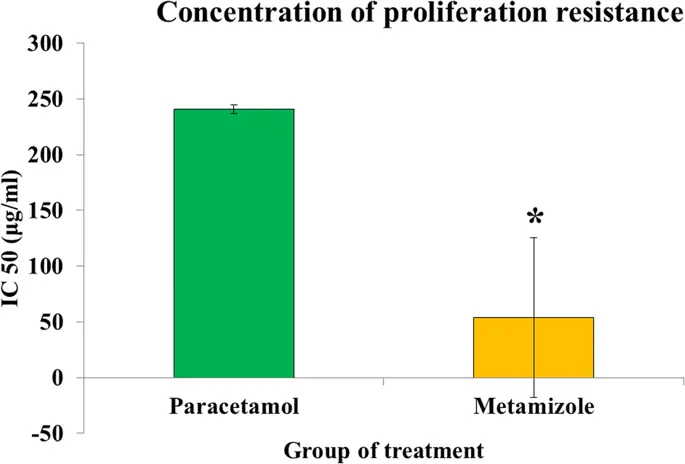

Метамизол имеет значительно более низкое значение IC50 по сравнению с парацетамолом (53, 9 ± 75, 9 против 240, 7 ± 4, 1 мкг / мл; р <0, 05), что указывает на то, что метамизол обладает более токсическим эффектом в подавлении пролиферации фибробластов по сравнению с парацетамолом ( рис. 5 ).

Концентрация устойчивости к пролиферации парацетамола и метамизола на клетках фибробластов толстой кишки крысы. Метамизол более цитотоксичен, чем парацетамол (*, р <0, 05)

Наши исследования in vitro показали, что метамизол был более цитотоксичен для фибробластов по сравнению с парацетамолом. Сообщалось, что парацетамол, обладающий умеренным противовоспалительным действием (14), требует большей дозы для получения той же пролиферативной ингибирующей способности, что и метамизол, который обладает более высоким противовоспалительным действием (15). В дополнение к значению IC50 для метамизола и парацетамола нам также необходимо знать максимальную концентрацию (Cmax) этих препаратов. Введение 1 г метамизола внутривенно даст значение Cmax 56, 5 мкг / мл (16). Принимая во внимание, что та же доза парацетамола будет давать только Cmax 19-22 мкг / мл (17, 18). При сравнении IC50 с Cmax каждой обработки значение метамизола IC50 (53, 9 ± 75, 9 мкг / мл) было ниже Cmax, так что концентрация ингибирования могла легко достигаться в крови. Однако это не относится к парацетамолу, где значение IC50 (240, 7 ± 4, 1 мкг / мл) было выше Cmax, поэтому будет трудно достичь концентрации ингибирования, если препарат вводился в терапевтических дозах. Таким образом, введение парацетамола в терапевтических дозах маловероятно, чтобы дать неблагоприятный эффект противовоспалительного действия, которое может быть вызвано метамизолом. Этот барьер пролиферации соответствовал предыдущим исследованиям (19, 20) об антипролиферативном действии НПВП на фибробласты крысы и человека. Антипролиферативные эффекты НПВП встречаются в прямых барьерах для увеличения ферментов циклооксигеназы в воспалительном процессе (20, 21). Воспалительный ответ будет активировать фермент СОХ-2, тем самым увеличивая синтез PGE2, который может ингибировать пролиферацию фибробластов (21, 22, 23). Антипролиферативные эффекты НПВП также сопровождаются барьерами для синтеза ДНК (18). Метамизол, обладающий неселективным ингибитором циклооксигеназы, будет подавлять активацию фермента СОХ-2, так что он может подавлять процесс синтеза ДНК и пролиферацию фибробластов толстой кишки крысы. Метамизол обладает более сильным антипролиферативным эффектом в линии клеток поджелудочной железы, Panc-1, чем парацетамол при самой высокой концентрации дозы 250 мкг / мл (24).